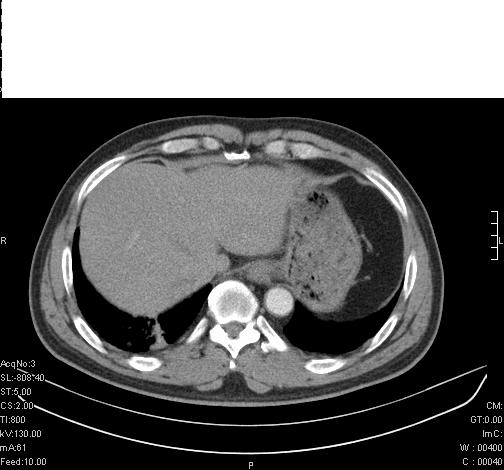

标题: CT6685:右肺阻塞性炎症,增强CT。

前几天,发了患者的平扫片,患者抗炎一周后增强扫描。右中叶病灶吸收明显,但下叶病灶未见明显吸收。右肺门可见结节影,看来凶多吉少

右肺下叶支气管管腔狭窄,管壁增厚,右下肺见斑片状高密度影,考虑右侧肺门中心肺癌伴阻塞性肺炎

右肺下叶散在的斑片状致密影,下叶支气管变窄。考虑:右肺慢性炎症。

右肺下叶支气管壁不规则增厚,右肺下叶有斑片状影分布。考虑右肺中央型肺癌伴右肺下叶阻塞性改变。建议支纤镜检查。平扫比增强较好显示了病变情况。

既然抗炎治疗有效,可继续治疗;右肺下叶支气管管腔狭窄,管壁增厚,右下肺见斑片状高密度影,右侧主支气管后见结节影(淋巴结?),肺癌不能排出。